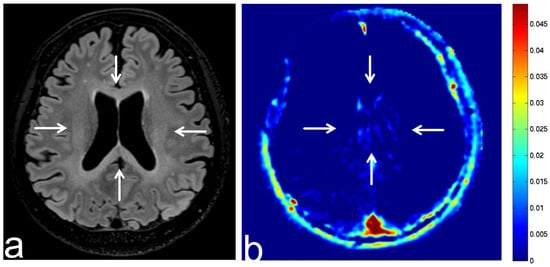

8.2. Leukoencephalopathy

8.3. Tuberous Sclerosis Complex

8.4. Progressive Multifocal Leukoencephalopathy